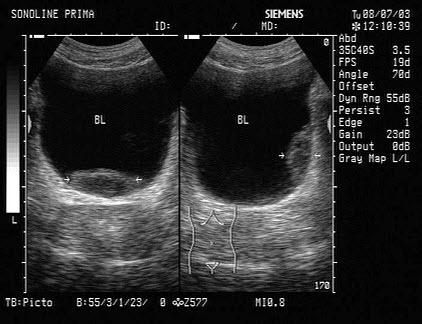

C.①④

D.②③